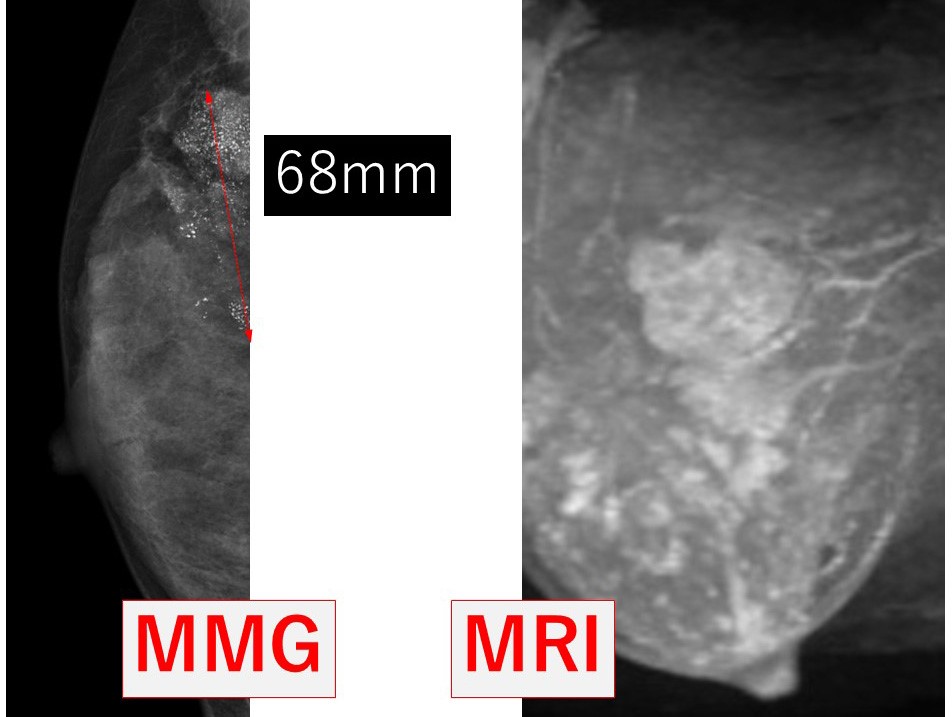

1. 画像所見

MMGで壊死型石灰化の範囲は68mm MRIでの拡がり